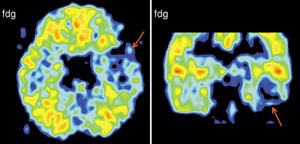

Именно наличие клиники во многом определяет возможности фундаментальных и прикладных исследований ИМЧ. Поэтому прежде всего несколько слов о ней. У нас прекрасные высококвалифицированные доктора и медсестры. Без этого нельзя: ведь мы на переднем крае, и нужна высочайшая квалификация, чтобы выполнять нерутинное, новое. У нас выполняются практически все стандартные манипуляции и наряду с ними и хирургическое лечение эпилепсии и паркинсонизма, проводятся психохирургические операции, в том числе и хирургическое лечение обусловленного героином обсессивно-компульсивного синдрома, знаменитая «пересадка мозга», точнее имплантация фетальной мозговой ткани, лечение магнитости-муляцией мозга, лечение афазии с помощью электростимуляции и многое другое. Накоплен десятилетний опыт клинических обследований с помощью позитронно-эмиссионной томографии. На рисунках приведена малая толика того, что может диагносцировать этот метод томографии. У нас лежат тяжелые больные, и мы стараемся помочь с помощью вышеперечисленных методов даже тогда, когда все остальные попытки были неудачны. Конечно, это удается не всегда. Но безграничных гарантий в лечении людей дать невозможно, а если кто-то дает их, это всегда вызывает очень серьезные сомнения.

Вообще, благодаря технике позитронно-эмиссионнной томографии (или сокращенно ПЭТ), стало возможно детальное изучение одновремено всех областей мозга, отвечающих за сложные “человеческие” функции мозга. Суть метода состоит в том, что малое количество изотопа вводят в вещество, участвующее в химических превращениях внутри клеток мозга, а затем наблюдают, как меняется распределение этого вещества в интересующей нас области мозга. Если к этой области усиливается приток глюкозы с радиоактивной меткой - значит, увеличился обмен веществ, что говорит об усиленной работе нервных клеток на этом участке мозга.

А теперь представьте, что человек выполняет какое-то сложное задание, требующее от него знания правил орфографии или логического мышления. При этом у него наиболее активно работают нервные клетки в области мозга, “ответственной” именно за эти навыки. Усиление работы нервных клеток можно зарегистрировать с помощью ПЭТ косвенно, по увеличению локального кровотока в активированной зоне. (Более ста лет назад было показано, что усиленная работа нервных клеток приводит к увеличению локального мозгового кровотока в этой области.)

Таким образом, удалось определить, какие области мозга “отвечают” за синтаксис, орфографию, смысл речи и за решение других задач. Мы предъявляем испытуемым различным образом организованные задания, при выполнении которых необходимо «задействовать» определенные свойства речи. Например, отдельные слова, предложения, связный текст. Сравнивая ПЭТ изображения, получаемые при этой деятельности, мы можем определить, где в мозге происходит обработка отдельного слова, где синтаксиса, а где смысла текста. Видны зоны, активирующиеся при предъявлении слов, неважно, надо ли было их читать или нет. Зоны, отвечающие за смысл текста, и другие. Интересно, и это будет рассмотрено ниже, что удалось обнаружить зоны, активирующиеся, чтобы «ничего не делать».

Рассеянный склероз - тяжелое хроническое заболевание головного и спинного мозга, поражающее сравнительно молодых людей 20 - 40 лет. Неясность многих вопросов возникновения и механизмов развития заболевания, трудности диагностики на ранних стадиях развития, разнообразие клинических вариантов течения с быстрой инвалидизацией, отсутствие эффективных методов лечения вывели изучение рассеянного склероза в круг наиболее актуальных задач современной медицины. В лаборатории нейроиммунологии Института мозга человека РАН разработан новый подход, позволяющий одновременно с использованием специфичных иммунологических методов оценки поражения клеток центральной нервной системы применять магнитно-резонансную и позитронно-эмиссионную томографию для визуализации патологического процесса. Принципиальная новизна состоит в том, что данный подход позволяет одновременно оценивать как системные аутоиммунные нарушения при рассеянном склерозе, так и локальные функциональные и морфологические изменения в центральной нервной системе. Комплексное нейроиммунологическое, инструментальное, клиническое обследование пациентов с рассеянным склерозом позволило установить важную роль поражений коры и подкорковых структур в механизмах развития этого заболевания.